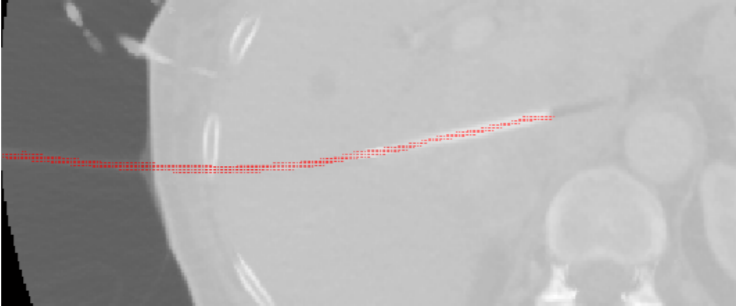

This thesis analyzes the realistic integration of objects into scenes. Commonly used methods,

as well as their conditions and restrictions are explained, followed by the question, whether an

automatic embedding process can be realized, even though the scene information is restricted

to one low dynamic range image only.

Therefore, different methods in the field of Style Transfers are discussed and implemented,

as they try to transfer image characterstics from one image to another. An additional, own

approache is then introduced, which uses an automatic white balancing algorithm to transfer

illumination information from the scene to and embedded object. The results are rated in a

user study about the visual quality of the computed images.

The results show, that none of the used methods produces very realistic integrations for all

scenes tested right away, but offer potential for further investigation.